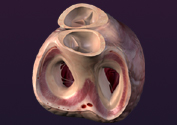

Sobre la visualización, los avances más destacados han ocurrido en la ciencia médica, tales como el de la actividad cerebral hasta el latido del corazón representados en un modelo virtual, y si bien estamos muy familiarizados con las imágenes en el computador considerado por Simone como uno de los dos motores que dieron inicio a la tercera fase, éstas han podido ser representadas con gran detalle y exactitud, desde hace muy poco tiempo y a pesar de que los ordenadores no son de naturaleza visual, procesan la información a través de un sistema binario de unos y ceros con el software indicado para procesar la información.

Modelos virtuales del corazón y del esqueleto de un niño16